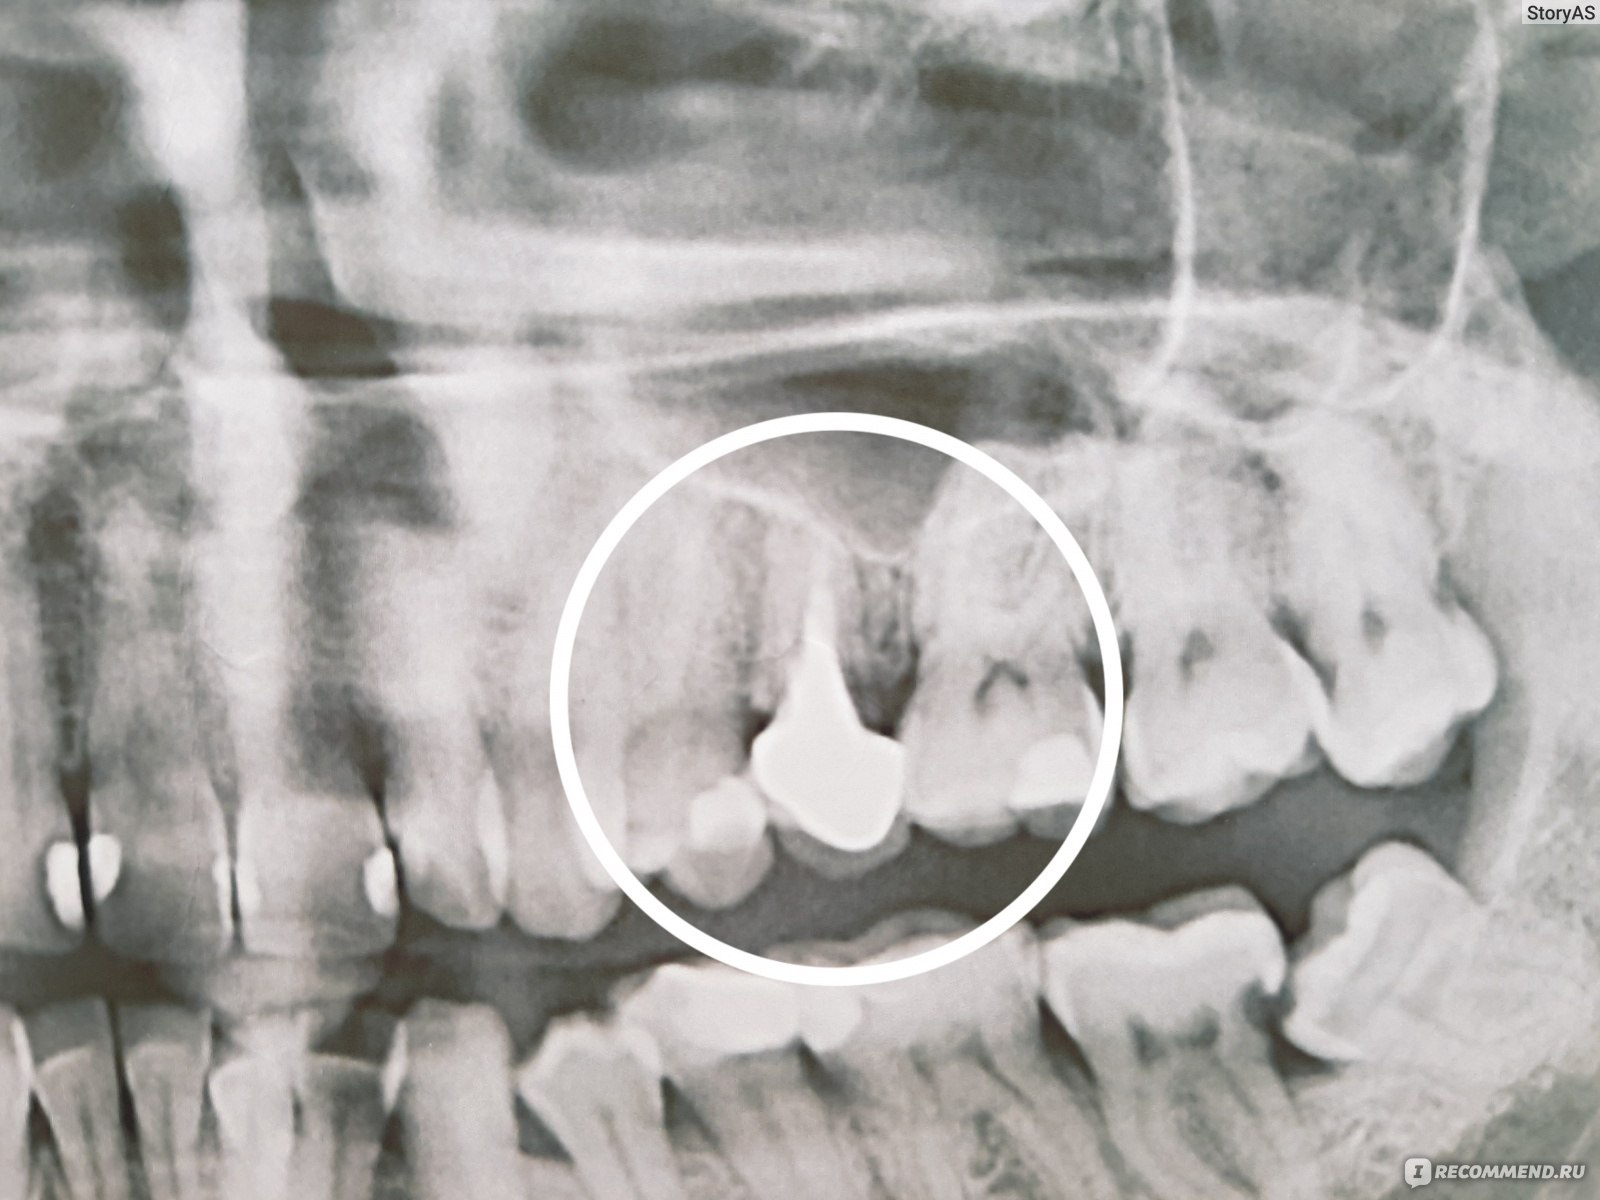

Дентальные снимки и диагностика кариеса